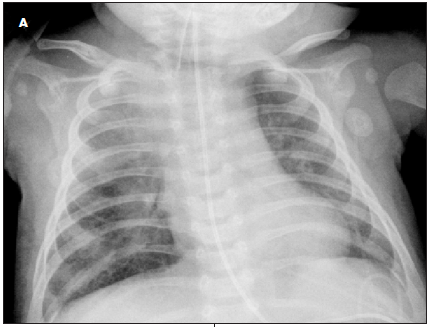

Results of a complete blood cell count showed lymphocyte predominance. Results of a basic metabolic panel were normal. The C-reactive protein level was 6.7 mg/L; erythrocyte sedimentation rate, 8 mm/h; hemoglobin level, 9.6 g/dL; and hematocrit, 29%. Polymerase chain reaction (PCR) testing was positive for Cytomegalovirus and negative for Toxoplasma, HIV, Epstein-Barr virus, and respiratory syncytial virus. A chest radiograph showed a hyperinflated right lung with a shift of the mediastinal contents into the left hemithorax, suggestive of air trapping and consolidation in the right upper lobe and hilar region (A); there was no thymic shadow. A CT scan of the chest showed diffuse mediastinal and right hilar adenopathy (B); this caused partial compression of the right main-stem bronchus. MRI showed bilateral pleural effusion with hilar lymphadenopathy and mediastinitis.